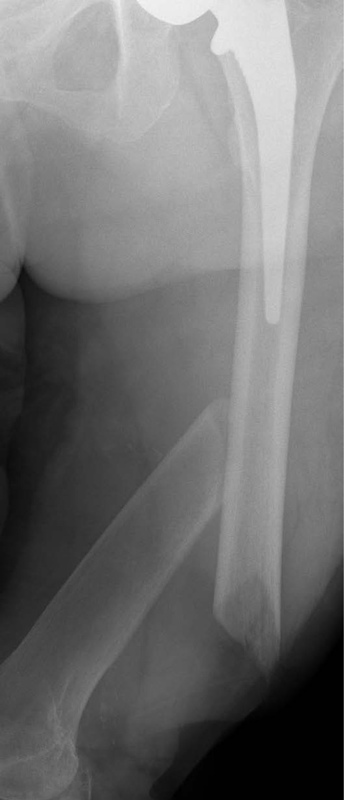

A 90-year-old patient presented with a periprosthetic femur fracture after a fall from a standing height fall. Patient is a community ambulator with no assistive walking device. X-rays revealed a long stem hip implant from a previous hemiarthroplasty. The fracture necessitated fixation and was treated operatively through a small incision in the medial distal femur. The guide wire was inserted to the tip of the stem before the implant was inserted. The IlluminOss implant was inserted, filled with liquid monomer, and cured with visible light. A plate and screw construct was placed laterally with screws extending into the hardened IlluminOss implant for support. Patient was allowed to weight bear as tolerated and reported no issues at follow up visit.